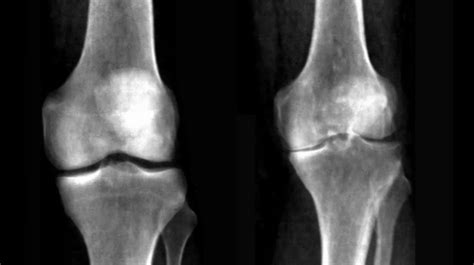

The most important concept to grasp is that a Knee Xray Normal result does not mean your knee is completely healthy. It only means that the bony structures appear normal. Many common causes of knee pain involve the soft tissues, which do not show up on a standard X-ray.

Because X-rays cannot visualize ligaments, tendons, or cartilage directly, you can have a completely normal-looking X-ray while still suffering from a severe ligament tear or a painful meniscus injury. This is why clinical correlation—matching your physical symptoms with the imaging—is so important.

• Early-Stage Arthritis: While severe arthritis shows up as a narrowed joint space on an X-ray, very early stage cartilage wear may not be visible.

Medicine relies on the combination of a patient’s story, physical findings, and diagnostic tests. A Knee Xray Normal is useful because it helps rule out dangerous bony pathology, such as fractures or bone tumors. Knowing what it is not helps clinicians narrow down what it could be.